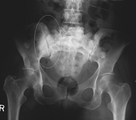

3D rendered CT of hip bone metastases.jpg

3D rendered CT scan of bone metastases of the hip bone, in a 60 year old woman with parotid gland cancer. Large lesions are seen on the hip on the more distant side. Involvement of the spine has caused a compression fracture.